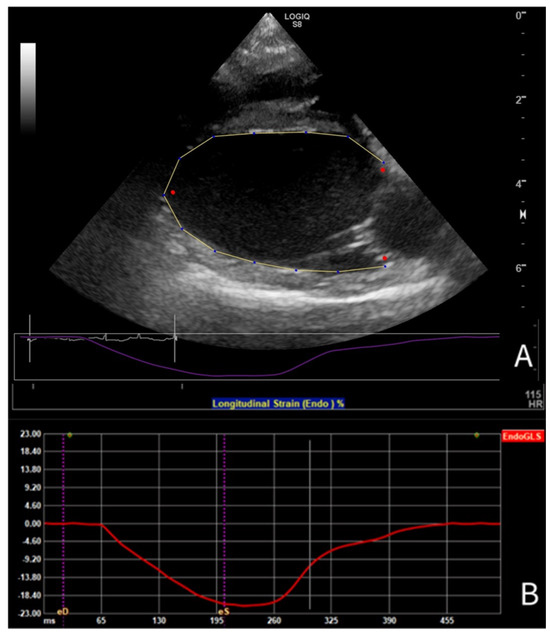

3.2. Results of Strain Analysis

3.5. Comparison of GLS Obtained from A4C and PLAX Views